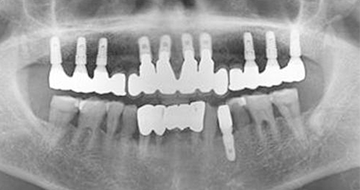

治療です。 前後写真

入れ歯の不快感を解消し、全顎インプラントを完成させます。

自然な機能と審美性の両方を満たす結果です。